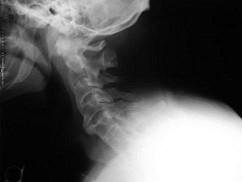

问题 男,21岁,下腰不适,晨起加重半年余,X线检查如图,请选出最可能的诊断 ( )

选项 A、化脓性脊柱炎 B、阻滞椎 C、脊椎退行性变 D、强直性脊柱炎 E、类风湿关节炎

答案 D